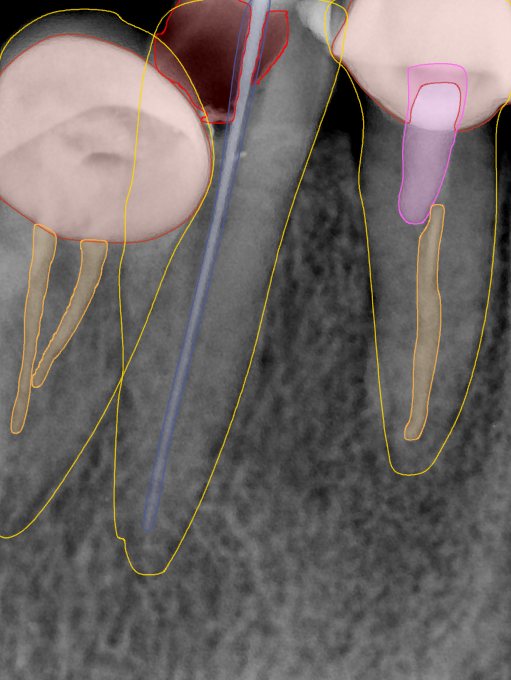

CR/DR 牙齿分割阶段记录

当前进展

- 完成了 CR/DR 牙齿相关分割训练

- 当前结果已经达到阶段预期,但仍有细节问题需要继续处理

相关测试

遇到的问题

- 训练过程中出现过 mask 下移问题

- 部分结果会出现 box 填充异常

- mask 边缘仍然有比较明显的锯齿感

第二版算法问题测试

| 第一版 | 第二版 | 是否解决 | |

|---|---|---|---|

![]() | ![]() ![]() 边角识别有问题 龋齿识别不全 牙髓识别不全 | ![]() | 解决 |

![]() | ![]() 边角识别有问题 识别信息有误 自查(牙冠识别不全) | ![]() | 解决 |

![]() | ![]() ![]() 边角识别有误 大范围填充识别遗漏 | ![]() | 解决 |

![]() | ![]() 识别信息不全 | ![]() | 解决 |

![]() | ![]() ![]() 边角问题 牙胶识别不全 牙冠识别不全 | ![]() | 解决 |

![]() 换图片 | ![]() | ![]() 牙冠部分稍微白了一些就识别成小范围修补,部分判断异常 | 部分解决,修复类略敏感,牙冠部分稍微白了一些就识别成小范围修补,部分判断异常。 |

![]() | ![]() ![]() 牙冠识别不全 牙髓不全 根尖炎龋齿识别有误 | ![]() | 解决 |

![]() | ![]() | ![]() | 解决 |

![]() 换图片 | ![]() | ![]() | 解决 |

![]() | ![]() 牙冠识别有误 | ![]() | 解决 |

![]() 换图片 | ![]() ![]() 边角识别有误 | ![]() 修复类敏感 | 部分解决,图像过白,导致修复类判断异常。 |

![]() 换图片 | ![]() 牙冠识别不全 | ![]() 修复类敏感 | 部分解决,图像过白,导致修复类判断异常 |

结论:修复类出现了不鲁棒的情况,后续需要加入轮廓的扩充数据进行增强。